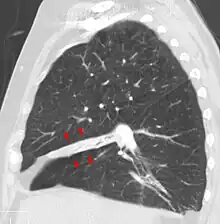

| Atelectasis of a person's right lung | |